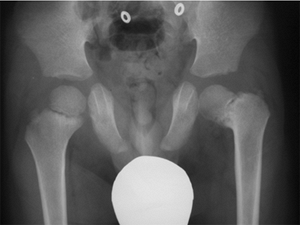

![]() |

Figure 27.16 Patient with classic exstrophy before closure. A: Clinical photo. B: Radiograph prior to closure. C: Radiograph after closure. (Courtesy of Paul Sponseller.)

usually symmetrically formed in patients with classic exstrophy. This

separation is typically approximately 4 to 5 cm at birth and increases

steadily with age (58) (Fig. 27.16B).